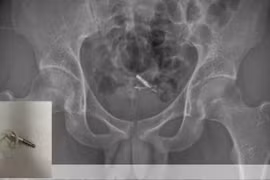

Nam thanh niên 19 tuổi đi tìm cực khoái bằng cách nhét dây tai nghe 3.5 mm vào niệu đạo. Tuy nhiên chàng trai này đã gặp sự cố ngay từ lần thử đầu tiên khiến cuộn dây mắc kẹt ở bên trong.